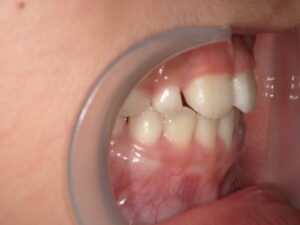

After

| 治療期間・回数 | 8ヶ月。11回。 |

| 治療方法 | リンガルアーチによる前歯の被害改善。 |

今回は骨格的には問題なく、前歯2本の歯の生える向きがずれてしまっているだけなので リンガルアーチにて上の前歯を前に押し出してあげます。

そうすることで下の前歯2本は何もしなくても自然と内側に引っ込みます。

装置が変形したり、壊れたりして治療期間が長引いてびいてしまいましたが だいたい3~4か月くらいで治ります。

成長してからではこんなに簡単には治りません。